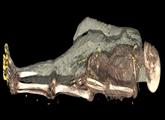

囧!埃及舞女木乃伊CT扫描发现竟是男儿身

近来,研究团队对一具1835年收藏进大英博物馆的埃及木乃伊进行了CT扫描,结果令人大吃一惊。 据大英博物馆古埃及与苏丹文化部门负责人John Taylor介绍,这具木乃伊刚被发现时,人们观察到其胸部...【